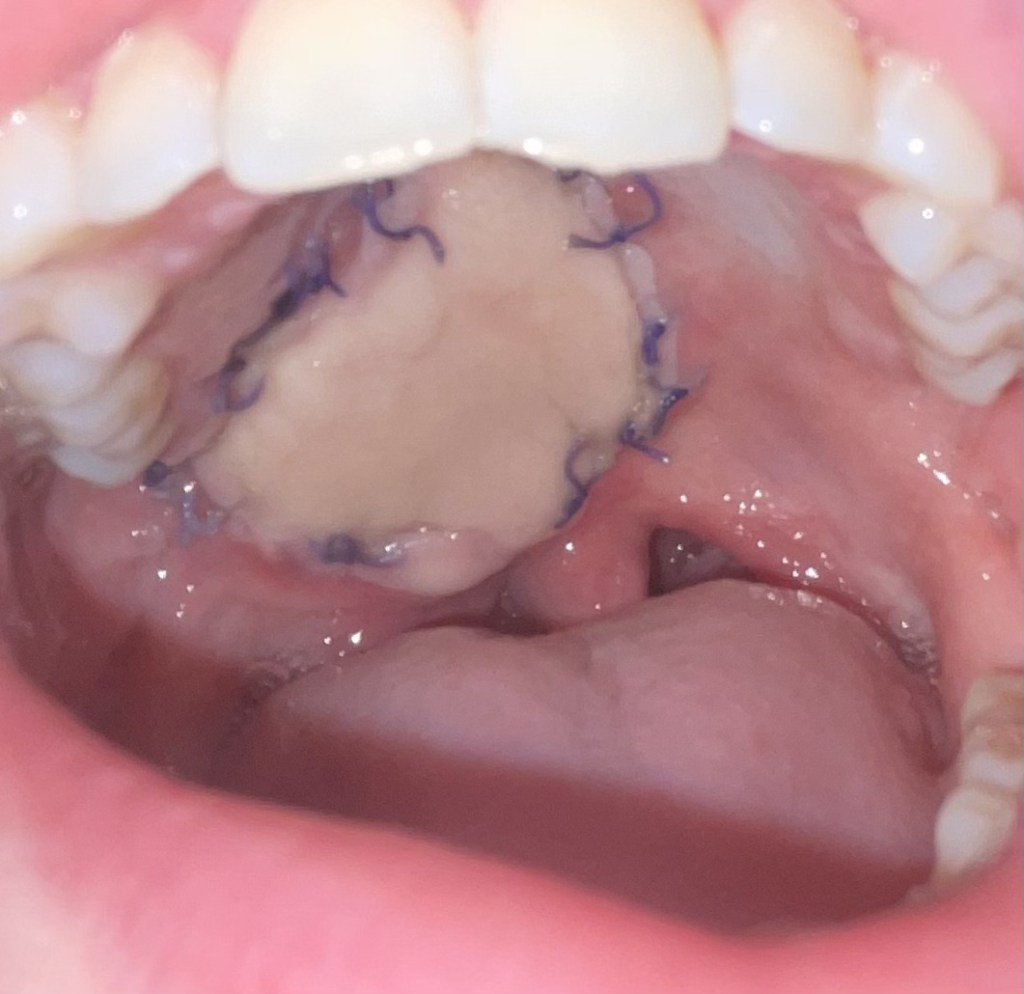

Here is the new skin in my mouth. (Before and after healing + radiation).

I have some hair’s starting to grow there. My surgeon mentioned laser treatment if it gets too crazy.